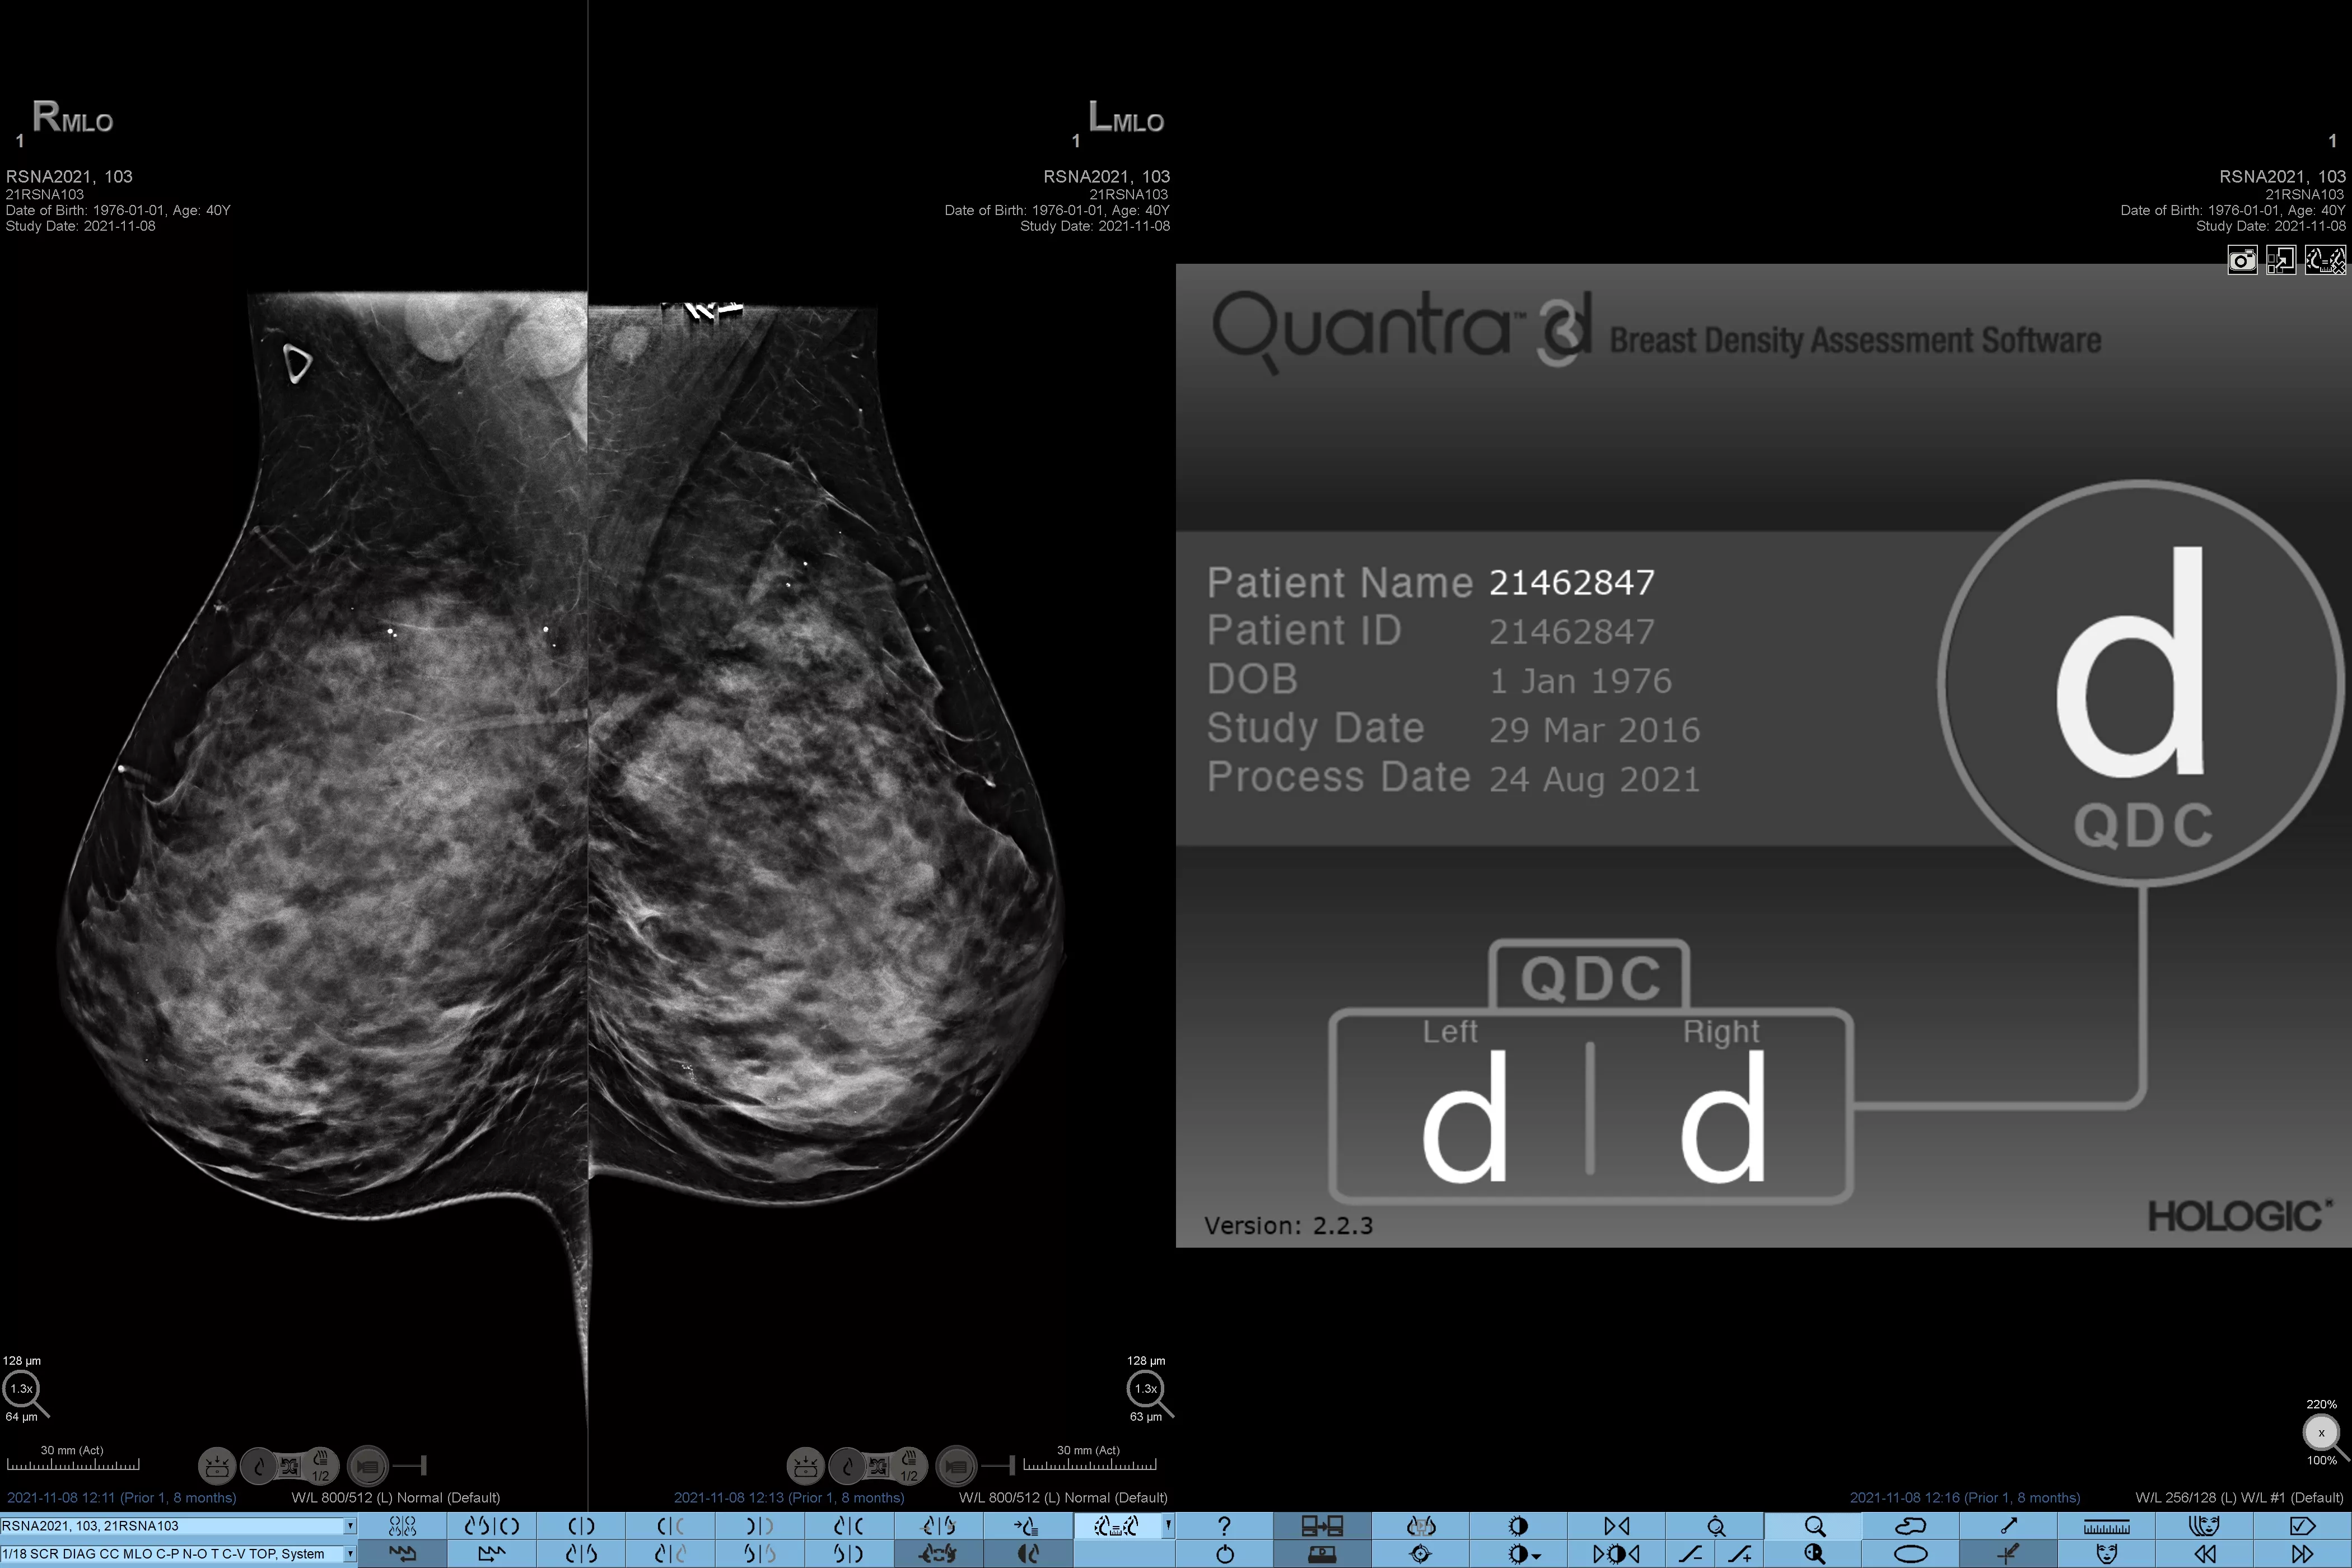

Man ved, at højere brysttæthed øger en kvindes risiko for brystkræft.1 Behovet for nøjagtige, objektive analyser er derfor afgørende. Quantra-teknologisoftwaren er drevet af maskinlæring og analyserer både 2D™ og tomosyntesebilleder for fordeling og tekstur af parenkymvæv. Den kategoriserer bryster i fire brystkompositionskategorier i overensstemmelse med vejledningen fra American College of Radiology (ACR) BI-RADS Atlas 5th Edition.2

* Scorer er baseret på ACR BI-RADS-kategorier på linje med den reviderede vejledning fra American College of Radiation (ACR) BI-RADS Atlas 5th Edition. Dette tager højde for mønster og tekstur i sammenlignet med volumen, når man bestemmer tæthed.

8. Breast composition categories as described in ACR BI-RADS Atlas.